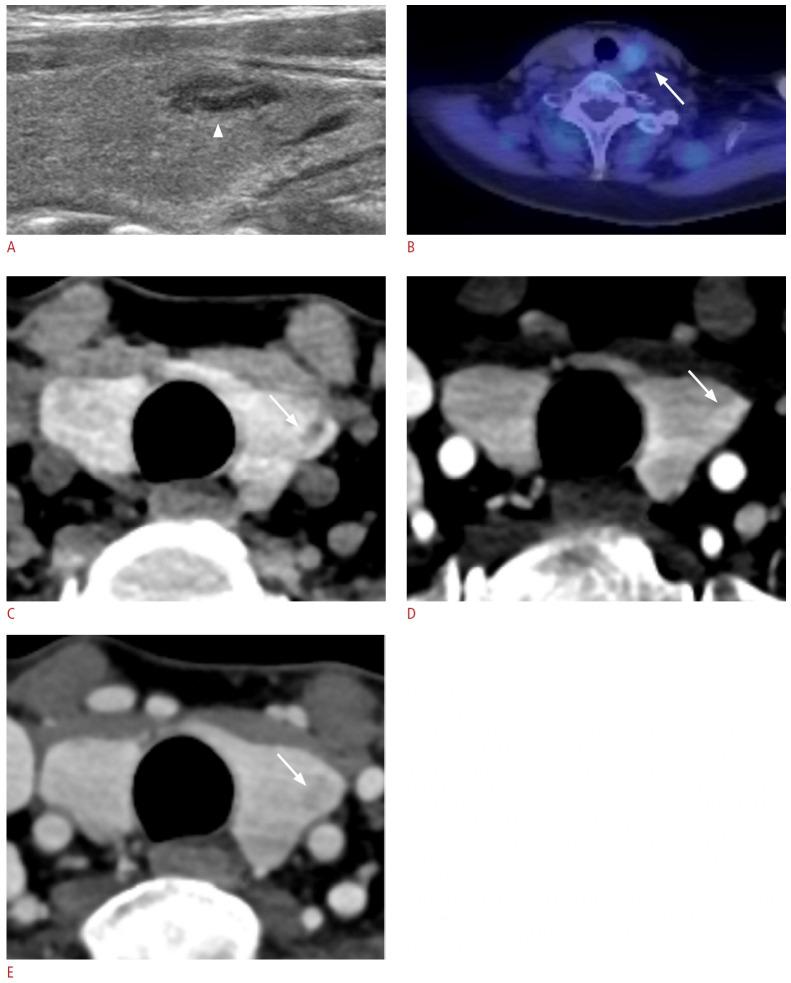

The parathyroid glands play a key role in maintaining calcium-phosphate homeostasis by secreting parathyroid hormone (PTH). Hyperparathyroidism, characterized by the inappropriate overproduction of PTH, is classified as primary, secondary, or tertiary according to its pathophysiology. Although diagnosis is principally biochemical, imaging is essential for accurately localizing hyperfunctioning glands. Precise localization allows for focused minimally invasive surgery, reduces the risk of persistent or recurrent disease, and avoids unnecessary bilateral neck exploration. Current techniques include high-resolution ultrasonography, 99mTc-sestamibi scintigraphy with single-photon emission computed tomography/computed tomography (CT), four-dimensional CT, magnetic resonance imaging, and positron emission tomography/CT with tracers such as 18F-fluorocholine. Parathyroidectomy remains the mainstay of treatment; however, recent advances in thermal ablation have expanded treatment options for patients unsuitable for surgery.

甲状旁腺通过分泌甲状旁腺激素(PTH)在维持钙磷稳态中起关键作用。甲状旁腺功能亢进症的特征是PTH分泌过多,根据其病理生理学可分为原发性、继发性或三发性。虽然诊断主要依靠生化检查,但影像学检查对于准确定位功能亢进的腺体至关重要。精确的定位有助于进行有针对性的微创手术,降低持续性或复发性疾病的风险,并避免不必要的双侧颈部探查。目前的技术包括高分辨率超声检查、99mTc-甲氧基异丁基异腈闪烁显像联合单光子发射计算机断层扫描/计算机断层扫描(CT)、四维CT、磁共振成像以及使用18F-氟胆碱等示踪剂的正电子发射断层扫描/CT。甲状旁腺切除术仍然是主要的治疗方法;然而,热消融技术的最新进展为不适合手术的患者扩展了治疗选择。